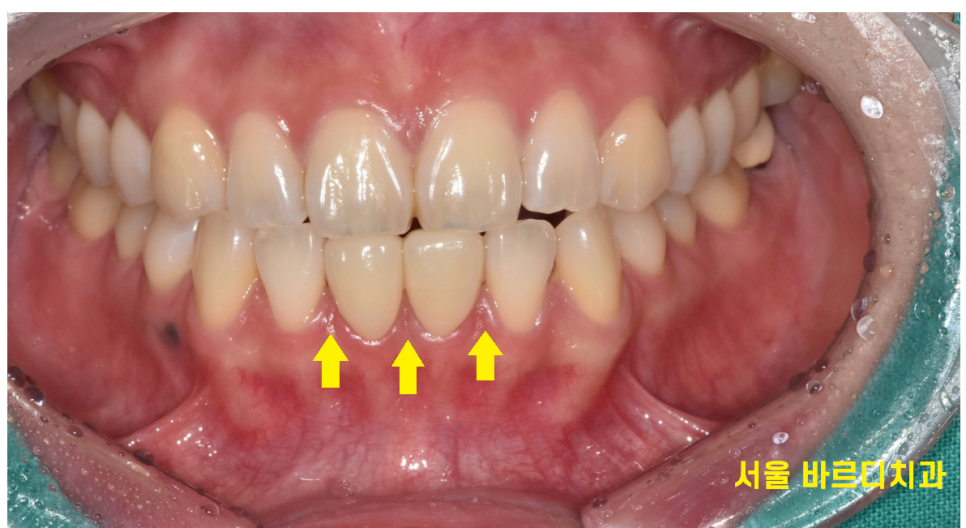

오늘 환자분은 윗니에 비하여

상대적으로 아랫니가 많이 벌어져 있었는데

벌어진 아래 앞니 4개나 되어

떼우는 레진 치료를 시행할 경우

치아가 너무 뚱뚱해 보일 가능성이 있었습니다.

또 다른 문제점으로는 양쪽을 다 떼워야해

작은 충격으로도 쉽게 떨어질 수 있었습니다.

벌어진 아래 앞니로 인해

공간이 보이는 곳은 3부분 이었습니다.

제가 판단했을 때 상대적으로 가운데 치아 2개가

작아 2개 정도만 치료해도

벌어져 보이는 것을 해결할 수 있다 생각했습니다.